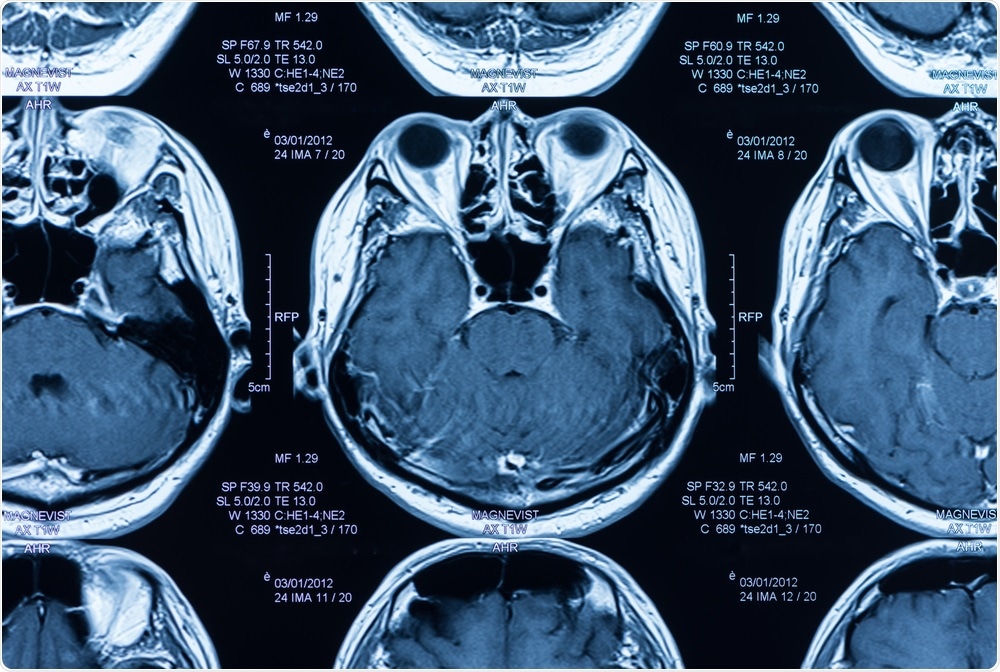

The research team analyzed magnetic resonance imaging (MRI) scanscreate jobs 51 | Shutterstock

The research team analyzed magnetic resonance imaging (MRI) scans and found that higher levels of body fat were associated with reduced volumes of gray matter and an increased likelihood of changes in the white matter.

For the current study, Dekkers and team analyzed MRI scans available for 12,087 participants (aged an average of 62 years) from the UK Biobank study and assessed the gray- and white-matter structure of their brains. They also measured the participant's levels of body fat using a method called bioelectrical impedance, which provides an estimate of body fat percentage.

Commenting on the value of MRI, Dekkers refers to the technique as an irreplaceable tool for understanding the link between neuroanatomical differences of the brain and behavior:

Our study shows that very large data collection of MRI data can lead to improved insight into exactly which brain structures are involved in all sorts of health outcomes, such as obesity.”